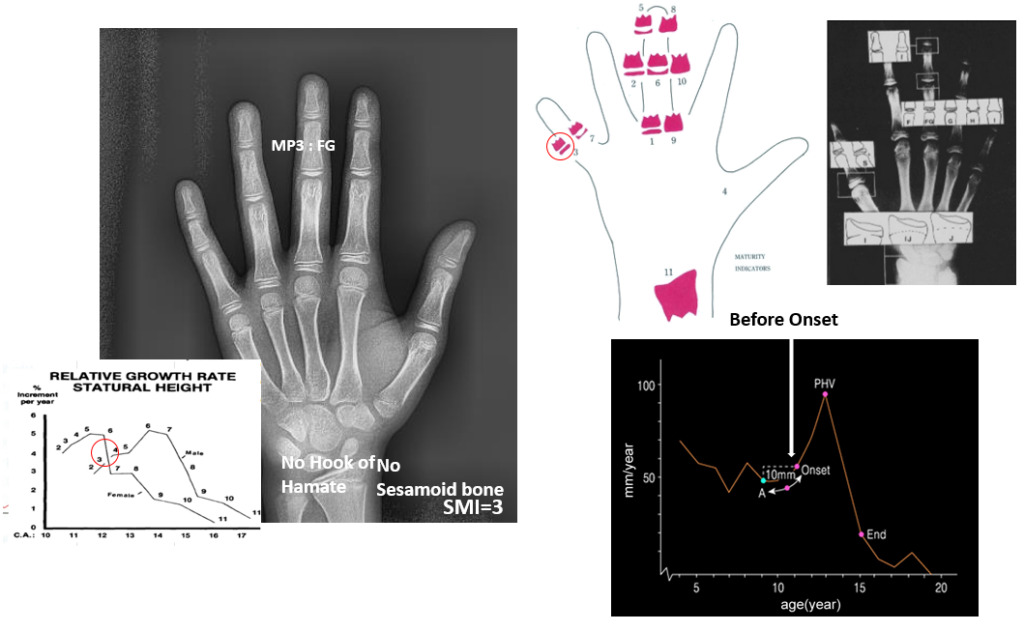

성장기 아이들은 뼈와 악궁이 아직 완전히 굳지 않은 상태라서, 이 시기에 교정을 시작하면 치아 이동뿐 아니라 턱뼈의 성장 방향까지 유도할 수 있습니다.